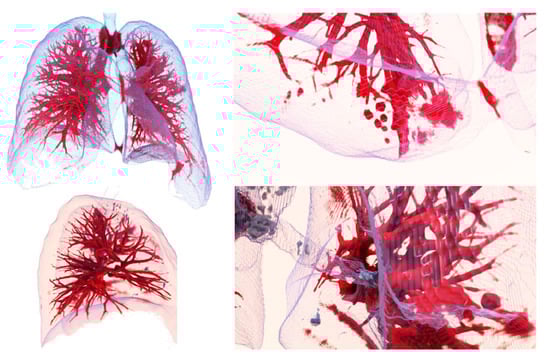

3.1. From dicom to 3D Models with Automatic Segmentation

3.2. Results Visualization

2.4. 3D Reconstruction and Storage